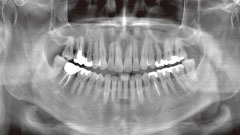

高精度な診断力で様々な歯科治療に貢献する

被曝量をより減らす

複数の撮影モード

幅広い撮影領域で

様々な症例に対応